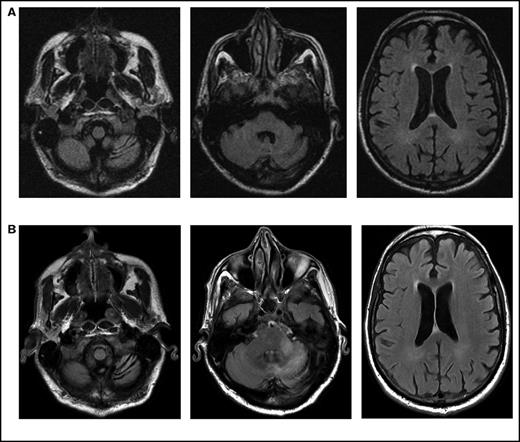

Initial symptoms included limb weakness (5 patients), visual loss (3 patients), cognitive impairment/behavior change (4 patients), and a cerebellar syndrome (4 patients). Magnetic resonance imaging abnormalities were restricted to the cerebrum in 12 patients; 2 patients had abnormalities restricted to the cerebellum and brainstem (Figure 1), and 2 patients had abnormalities in both the cerebrum and the brainstem and cerebellum.

Serial imaging of a patient diagnosed with CLL. Cancer-directed therapy included >6 months of rituximab and idelalisib. (A) Initial magnetic resonance imaging performed 2 months after the onset of headaches and balance disturbance (gait instability and repeated falls) depicting the asymmetric atrophy of the left cerebellum, which was not present in imaging performed 7 months earlier (not depicted). Fluid-attenuated inversion recovery (FLAIR) signal abnormalities are not present elsewhere. (B) Imaging repeated 3 months later (1 month prior to death) showing the continued atrophy of the left cerebellum with new confluent areas of FLAIR signal throughout the left cerebellum and left cerebellar peduncle without enhancement. Again, no FLAIR signal abnormalities are seen in the cerebrum.